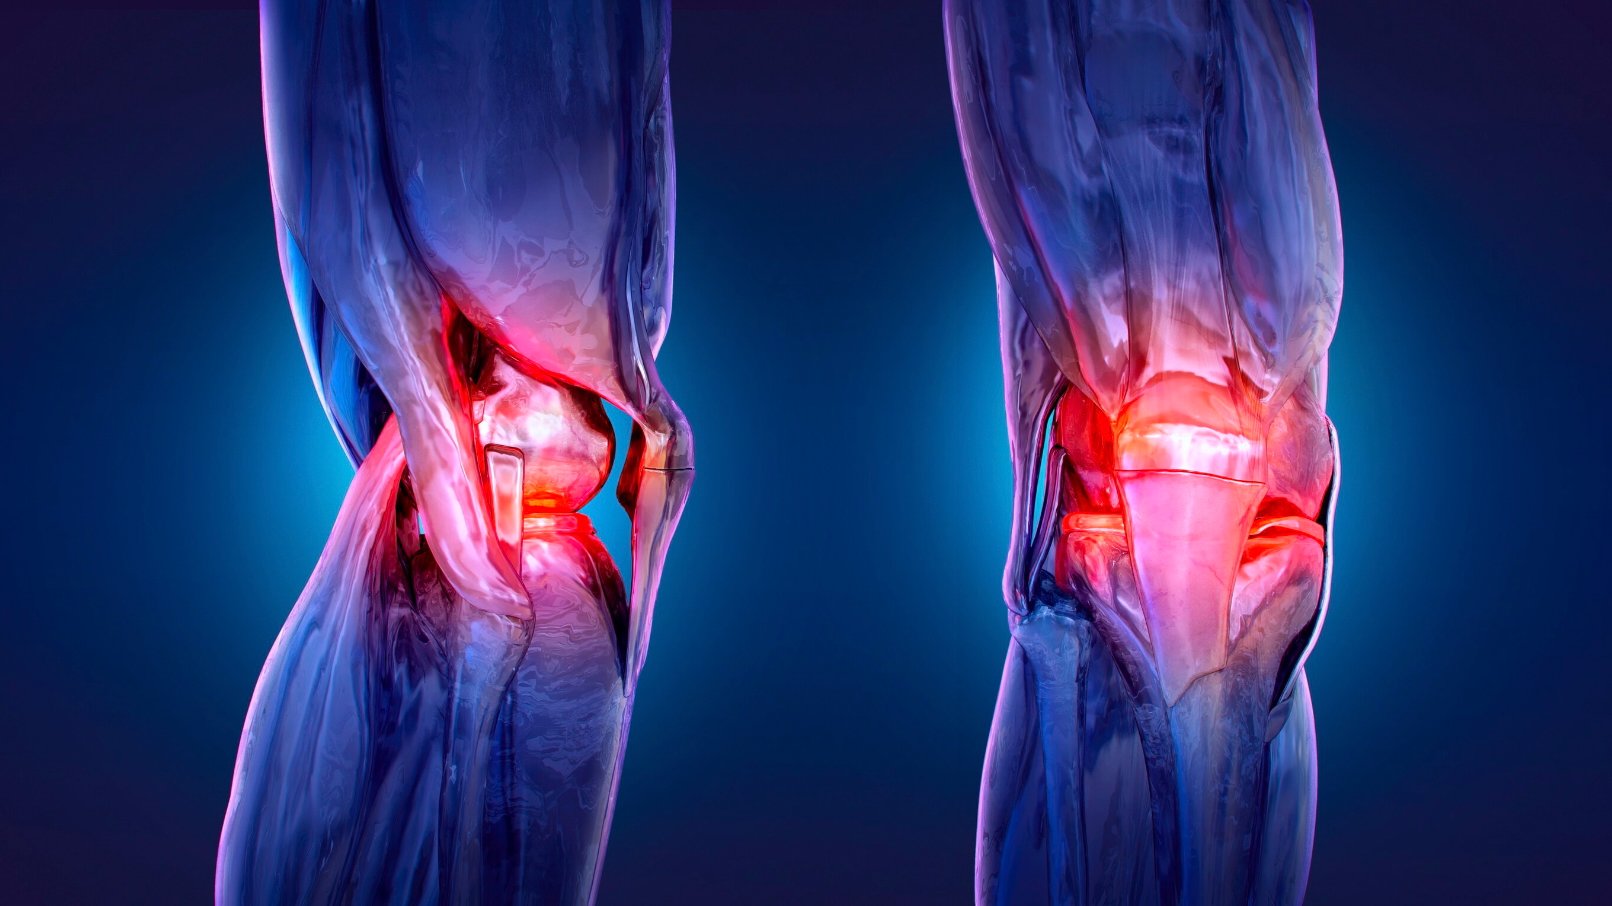

Vì sao đầu gối anh em phát ra tiếng rắc và điều đó có thật sự đáng lo ngại?

Như vậy, nếu đầu gối anh em phát ra âm thanh mỗi khi đứng lên hoặc bước đi, thì nó rất bình thường trừ phi đi kèm theo đó là những cơn đau kéo dài. Và dù ở độ tuổi nào, anh em cũng nên chủ động bảo vệ khớp bằng cách điều chỉnh lối sống, ăn uống khoa học và duy trì vận động hợp lý.